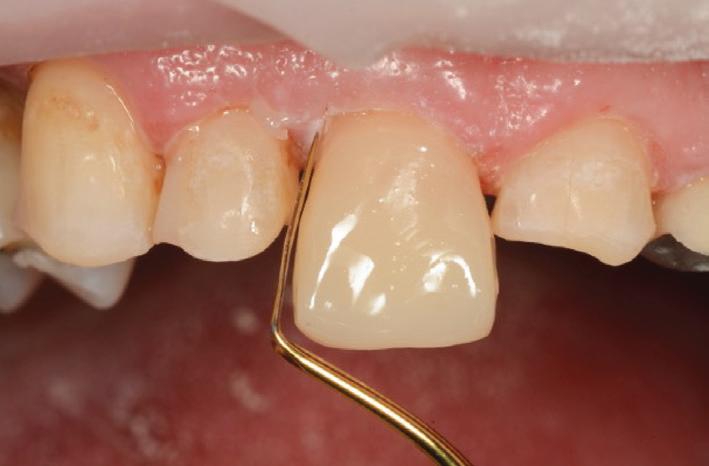

Finally, a superficial layer of enamel shaded composite (A2E) was applied (Fig.12), shaped and cured, before reshaping of the tooth was performed with OptidiscTM system (Fig. 13).

Restoring the Central Incisor (#11) first, enabled the Author to establish the midline position and correct length and form for the teeth. The remaining teeth were then built up one at a time, using the initial buildup of #11 as a guide (Figs. 14, 15).

Natural colours and a beautiful, life-like surface polish were produced with the multilayered application of this nanocomposite – HarmonizeTM (Fig. 19).

Importantly, the stability of the occlusion was re-established with creation of occlusal contacts on each tooth, and the re-introduction of canine and incisal guidance, to control lateral and protrusive forces (Figs. 20, 21, 22, 23).